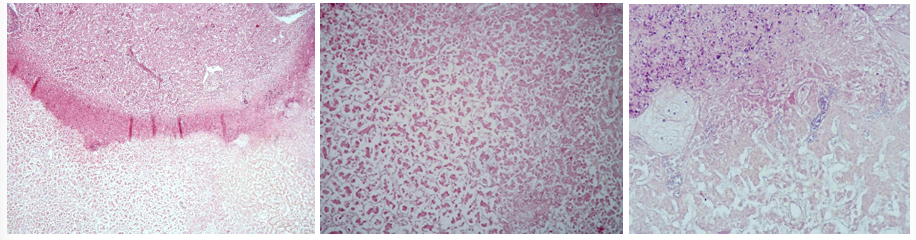

This is?

285 - Dystrophic calcification (infarctus renis anemicus)

Description: No regular oval focus in cortex of kidneys, red-violet center (calcification). Relatively mature granulation tissue of fibrocytes and collagenous fibers. At margin we can observe infiltration by lymphocytes and histiocytes.

Etiology: Caused by deposition of calcium into the tissue. Prominent in chronic tissue destructive lesions such as tuberculoid granulomas in cattle (Tuberculosis)

Pathogenesis: Dystrophic calcification implies tissue damage, degeneration, death of cells or denaturation of proteins in tissue, typically occurring in areas of necrosis.

Hemosiderosis of spleen (Liesegang)

Description: Stained by Liesegang to prove hemosiderin. In the red pulp of the spleen, excess hemosiderin is stained blue. It is present as lumps in macrophages (siderophages, siderocytes) or encrusted in fibers of connective tissue.

Etiology: Occur during excess intravascular destruction of erythrocytes (infectious, parasitic diseases and blood poisoning). Increased concentration in one area is also an indication of previous hemorrhages.

Pathogenesis: Hemosiderin is a iron-containing pigment found in macrophages and is prominent as a lesion (hemosiderosis). If excess iron is absorbed, or a lot is released from hemolysis, the levels in macrophages will increase and accumulate. In older dogs, there are often brown, raised, granular lesions on the edge of the spleen. These contain iron, ceroid and hemosiderin, and probably represent previous hemorrhages.